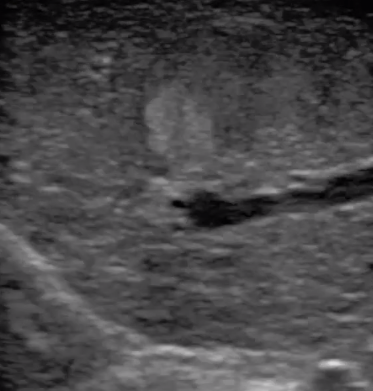

腹腔鏡下 肝臟占位

腹腔鏡超聲是超聲技術(shù)和腹腔鏡技術(shù)的融合,腹腔鏡超聲降低了對超聲探測深度的要求。由微小切口進入手術(shù)部位,多角度彎曲可選擇,降低手術(shù)難度及風(fēng)險;與受檢組織器官直接接觸,有效避免氣體干擾。

應(yīng)用科室:麻醉科、手術(shù)室、普外科、泌尿外科、婦產(chǎn)科、腫瘤科、介入科等